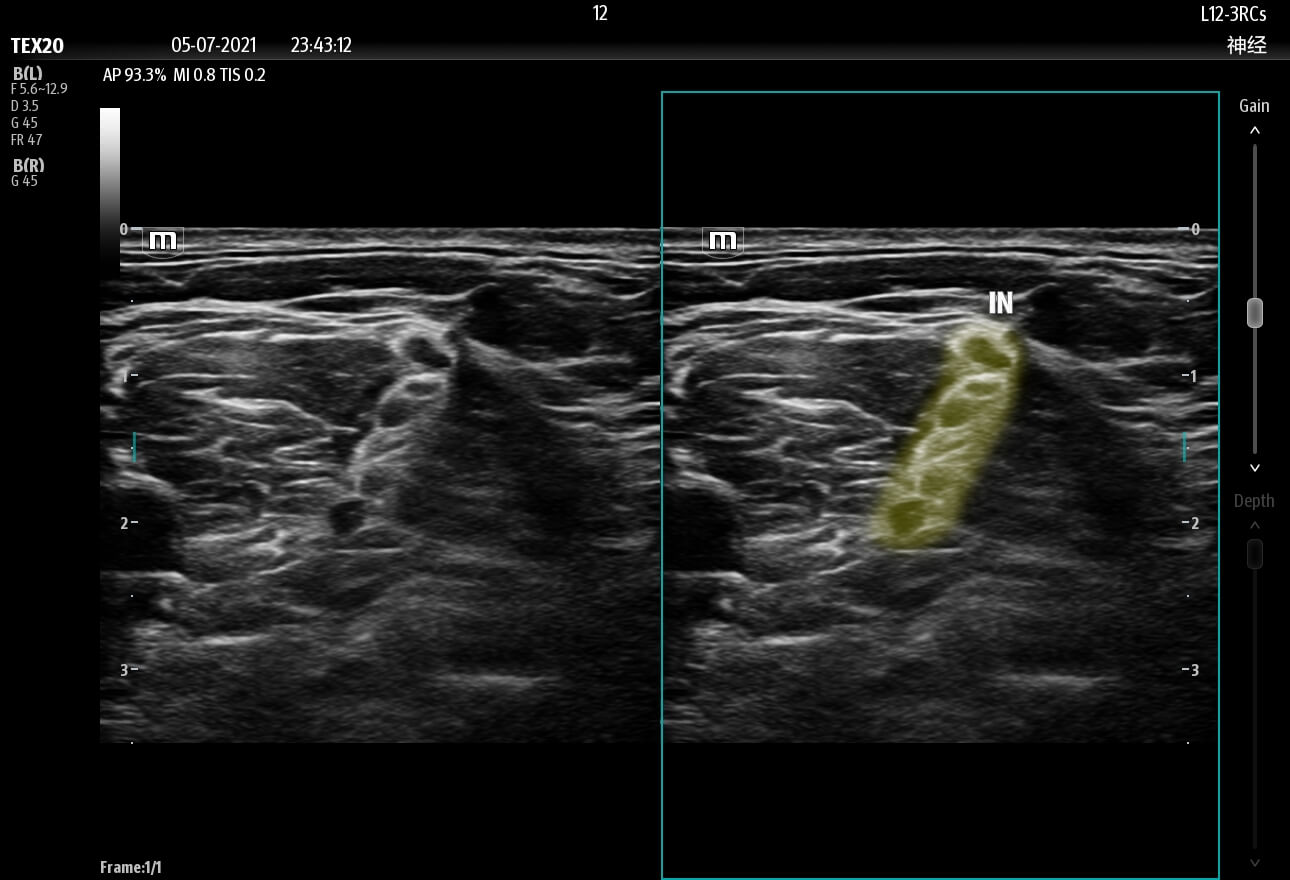

Needle Guidance